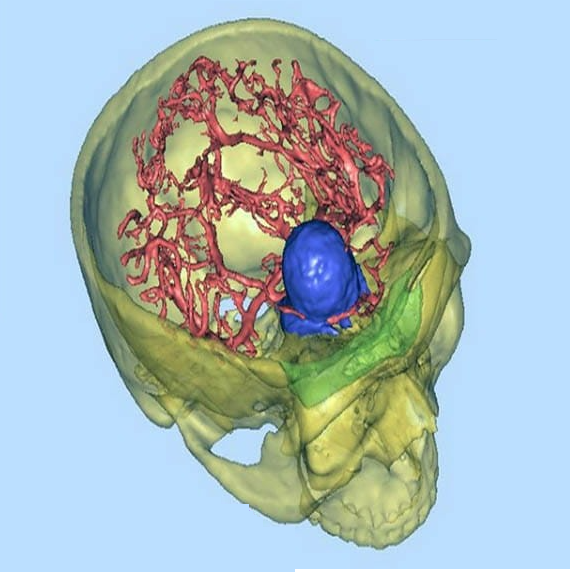

برای اینکه از علم عقب نمانم، به کشور های مختلف سفر کردم ...

در سمینار و کنفرانس های متعدد شرکت کردم و روش های نوین را آموختم و در کنفراس های داخلی به دیگر عزیزان آموزش دادم